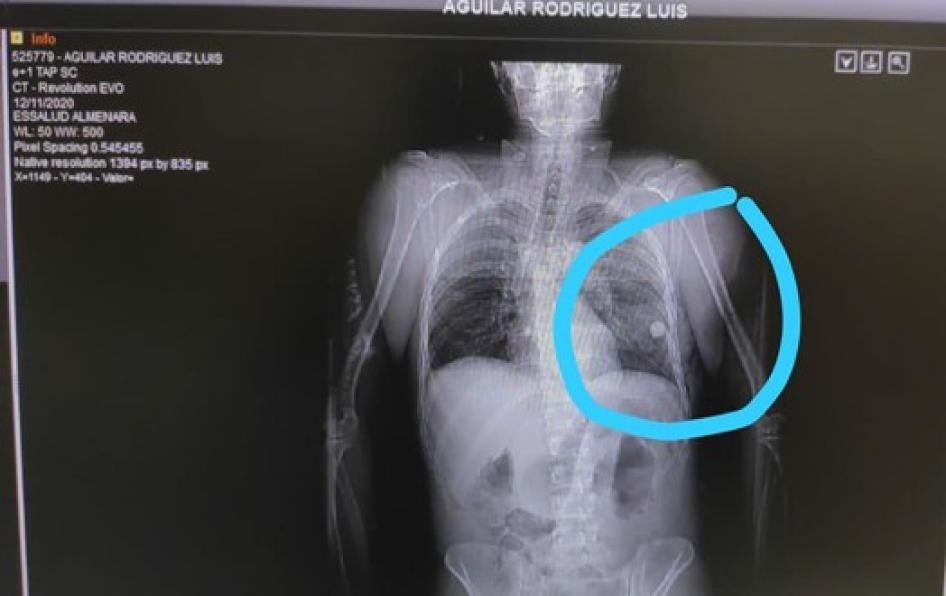

- Two protestors found Luis Aguilar Rodríguez, 26, bleeding from the chest on Abancay Avenue on November 12 and took him to a hospital, his mother said. After surgery, doctors told her that the object that had hit his chest, damaging his lungs, was a glass marble, which they removed. Aguilar Rodríguez left the hospital on November 30.